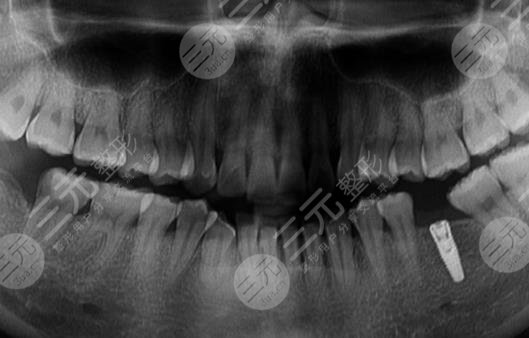

因为我的牙齿整体情况还行,就是有点松,然后医生先是给我的牙齿做了整体的检查,拍了片子确定能够进行种牙手术后,才为我进行了方案的设定,种牙前先对我的牙齿进行详细的情况,然后是种植体的安装,因为有麻醉所以没有什么感觉,但是能够感觉到在骨头上面做东西,安装好后要等2个月左右才会进行下一步的工作。

大家可以看一下,我进行完种植牙手术后的样子,是不是还是较为的不错的?看起来也很自然,较重要的是变得特别的坚固,像之前因为牙齿的问题,不敢吃的那些食物都可以吃了,又可以天天去吃我喜欢吃的大骨头了,心里面真的是特别的开心。